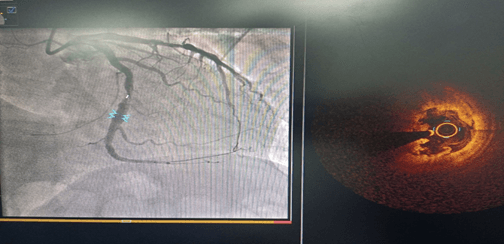

術(shù)前CAG示:左主干閉塞 IABP支持下開通閉塞血管

術(shù)前IVUS示最小管腔面積2.00mm2;術(shù)后IVUS示最小支架面積7.61mm2